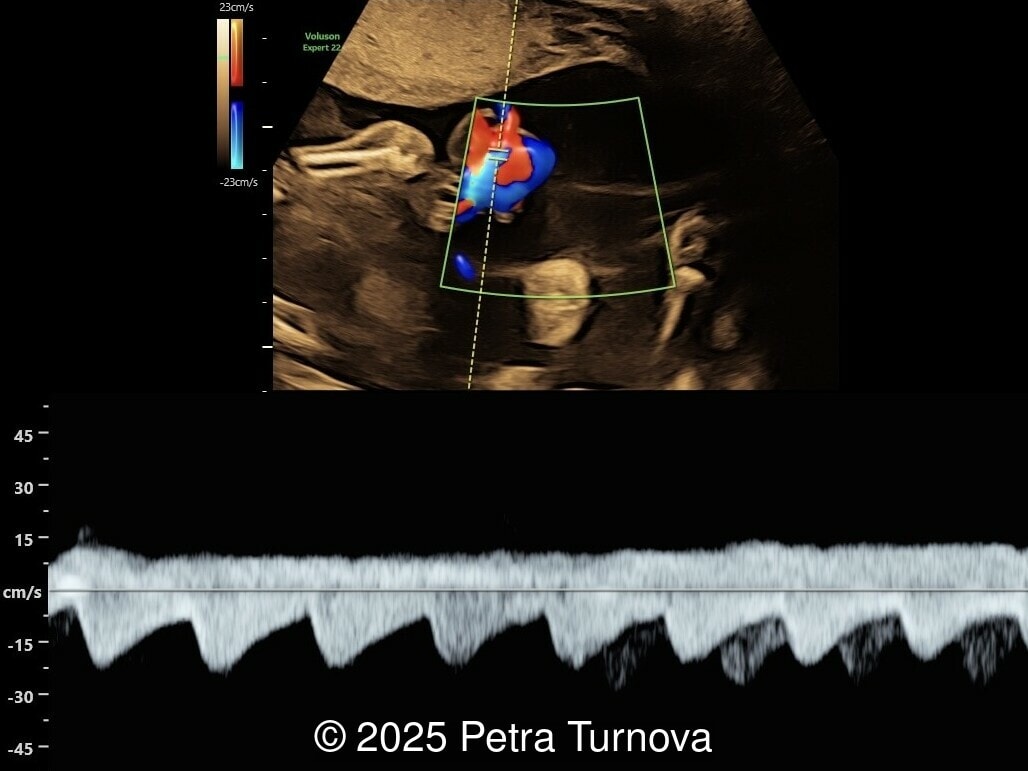

We present a case of cord entanglement. Unfortunately, the pregnancy ended in fetal demise two weeks after our exam.

Monochorionic monoamniotic pregnancy represents the rarest type of multiple gestation, accounting for approximately 1% of all twin pregnancies. The risk of fetal mortality in this type of pregnancy is around 80%. In the case of twin pregnancies, the fetuses share a common placenta, amnion, and chorion. The chorionicity and amnionicity are determined by the timing of zygote division. If the zygote divides between days 8 and 12, a monochorionic monoamniotic pregnancy results. A specific complication uniquely associated with monoamniotic and monochorionic pregnancy includes conjoined twins and cord entanglement.

Cord entanglement can be visualized from the 12-13 weeks of pregnancy. The risk of cord events increases in cases of close cord insertion on the placenta. Some studies have confirmed that intermittent occlusion is associated with neurological morbidity, while prolonged occlusion is fatal. Ultrasound may visualize intertwined umbilical cords. On Doppler flow studies, intermittent or persistent notching of the umbilical artery may be present. This phenomenon is typically observed in abnormal uterine artery flow associated with placental insufficiency and is less frequently seen in umbilical artery flow disorders. Based on physical calculations, it has been shown that notching does not occur unless there is a reduction in tube diameter below 75%. Therefore, notching is present in cases of significant flow reduction.